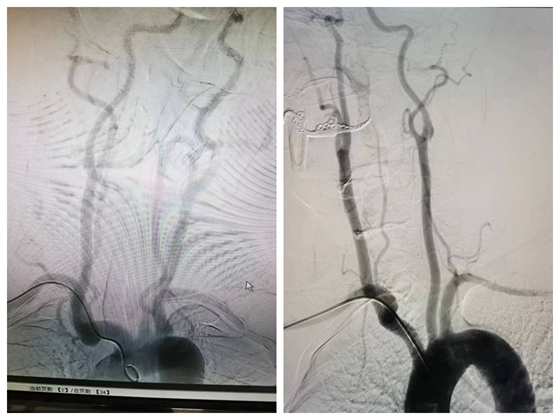

神经内科主任周文斌、主治医师丁源、医师刘鑫查房后,立即为患者完善头部核磁,根据患者症状、体征以及辅助检查,明确诊断为急性脑梗死,颅内血管MRA提示双侧椎动脉及基底动脉节段性狭窄,有行脑血管造影指征,需进一步评估患者颅内血管情况。主任医师张先龙为李先生和妻子介绍可以开展新技术,经桡动脉行脑血管造影检查,术后可以从介入手术室走回病房,无需卧床休息且舒适度高,恢复快,可以避免长时间卧床引起的不适和痛苦,如:腰痛,尿潴留等,同时也避免了卧床期间大小便需要他人护理的尴尬。

随着影像技术的发展,越来越多的无创技术如CTA、MRA等用于临床评估脑血管的情况,但选择性脑血管造影作为一种有创的脑血管检查,仍是目前评估脑血管的“金标准”,经股动脉入路全脑血管造影术已经成为常规方法,就桡动脉来说血管变异及迂曲多,在手术技术方面仍存在一些难度,但对患者术后护理更方便,舒适度更高。患者及家属对医护人员表示由衷感谢。

主任医师张先龙表示:经桡动脉全脑DSA较经股动脉具有诸多优点,一是对穿刺局部损伤小,出血少,术中及术后并发症少且轻微,术后护理方便安全,二是术后即可下床活动,舒适度好,患者易于接受,尤其对于老年人,三是术后不需长时间制动,四是对于股动脉狭窄/闭塞或既往曾发生过股动脉严重并发症的患者,可以作为另一备用选择。由于该术式的诸多优点,大大地提高了患者接受脑血管造影这一血管检查金标准的程度。